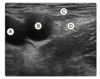

What is the first line treatment for this patient?

Pericardiocentesis

Cardiopulmonary resuscitation

14g angiocath insertion at the 2nd intercostal space midclavicular line

Chest tube insertion

14g angiocath insertion at the 2nd intercostal space midclavicular line

Emergency treatment of a tension pneumothorax includes insertion of a 14g angiocath into the 2nd intercostal space at the mid-clavicular line or the 4th or 5th intercostal space at the anterior axillary line. This will release the tension and relieve hemodynamic instability, but not the underlying pneumothorax.

Chest tube insertion is the definitive treatment. Pericardiocentesis is a treatment for pericardial tamponade. CPR should not be started based on a CXR alone.